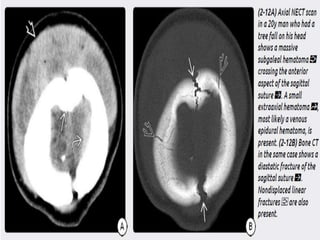

1) Epidural hematoma- two types : arterial EDH and

venous EDH. EDH r uncommon but r potentially

lethal. 90% EDH r arterial , 10% r venous. Venous

EDH r sec. to a fracture that crosses dural venous

sinus (transverse/sig , SSS)

a) Arterial EDH – d/t direct trauma to skull that

lacerates an adjacent artery(mc’ly-mma)

mostly unilateral and supratentorial. Squamous

portion of temporal bone is the most common site.

Biconvex in shape, doesnt crosses suture line, but

if fracture crosses suture line……

 CT - classic (arterial) EDHs is a hyperdense (60-

90 HU) biconvex extraaxial collection (2-18).

Presence of a hypodense component ("swirl"

sign) is seen in about one-third of cases and

indicates active, rapid bleeding with

unretracted clot.

“Buckling" the gray-white matter interface

inward.

Air in an EDH occurs in approximately 20% of

cases and is usually associated with a sinus or

mastoid fracture.